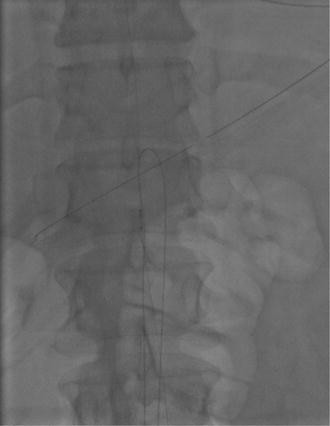

Endarterectomy and stenting of the descending aortic flap. Vascular access was obtained via the right common femoral artery. Wires were placed in both the true aortic lumen and the false lumen under intravascular ultrasound (IVUS) guidance via the external iliac artery. IVUS of the aorta showed that in the thoracic aorta the true lumen was widely patent and large in caliber. In the sub-diaphragmatic segment at the level of the visceral vessels the true lumen became quite small before enlarging again in the infrarenal aorta (Panel A). An endovascular endarterectomy was performed from T11 to the aortic bifurcation. A 6 F Pioneer® Plus IVUS reentry catheter (Medtronic CardioVascular, Santa Rosa, CA) was used to create a path from the true lumen to the false lumen at T11 (Movie 1). This wire spanning both lumens was snared in the false lumen using a catheter advanced from the right common femoral artery. Both ends of a 0.025″ Terumo® guide wire (Terumo Europe N.V., Leuven, Belgium) were externalized and pulled together to the iliac bifurcation to perform the endarterectomy (Movie 2). IVUS of the aorta showed that the infra-diaphragmatic aorta now comprised a single lumen. The right renal artery and mesenteric vessels filled briskly but the aorta was occluded at the just below the inferior mesenteric artery as a result of functional endarterectomy of the infra-diaphragmatic aorta. Two 8 × 57 mm VisiPro™ balloon-expandable peripheral stents (Covidien, Dublin, Ireland) were deployed in a kissing fashion, extending from the infrarenal aorta into the right and left common iliac arteries. They were postdilated with 10 and 12 mm balloons. Further overlapping stenting was required to maintain adequate distal flow. Femoral and pedal pulses were bounding post-procedure